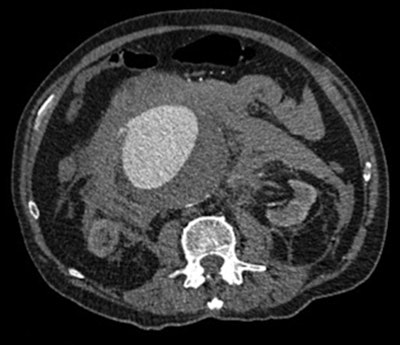

An example of a CT image of a leaking abdominal aortic aneurysm. Image courtesy of Dr. David Howlett.The problem with abdominal CT

Acute abdominal pain outside of the trauma setting is common in the emergency department, with a wide spectrum of underlying causes for which CT is used as an integral part of surgical triage, the authors noted.